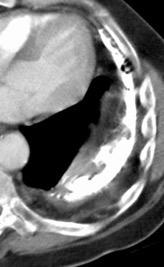

Absceso pulmonar por Neiseria y Est. Viridans. “Borde mal definido”.

Cavidad en el centro de la densidad

Empiema pleural en adicto. “Borde bien definido”.

Cavidad en el ápice

DD et al . Differentiating abscess and empiema: Radiography and computed tomography. AJR.1983